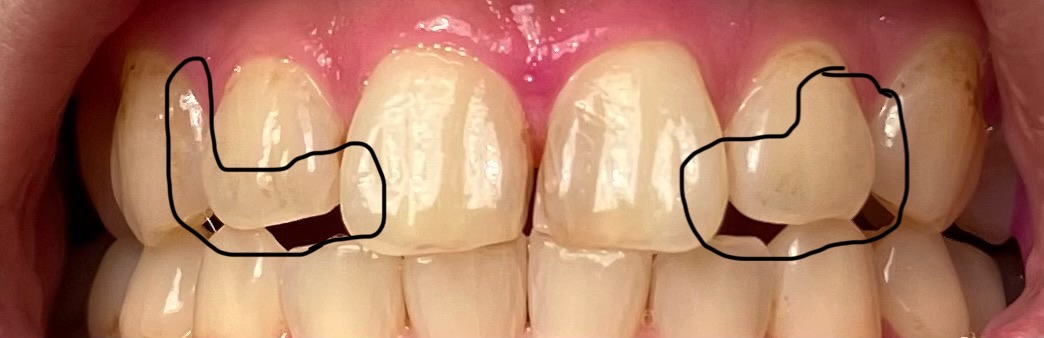

前側の歯が模様のように暗く透けてきているような感じがしています。

(添付画像の黒で囲った辺りが特に気になります)

最近は染色をした時に、画像のマークしたあたりに、うっすらと歯垢が残っています。

が…しかし、この2ヶ月くらいでうっすらと透けが広がってきている…?影ができている…?

写真拝見いたしましたが正常の範囲だと思います、食生活歯磨きとも大きな問題はなさそうに思います、ただオーバーブラッシングには気を付けてください。